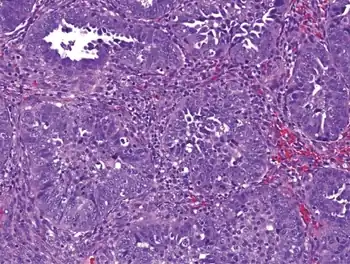

| Opsoclonus as suspected paraneoplastic syndrome of endometrial cancer | |